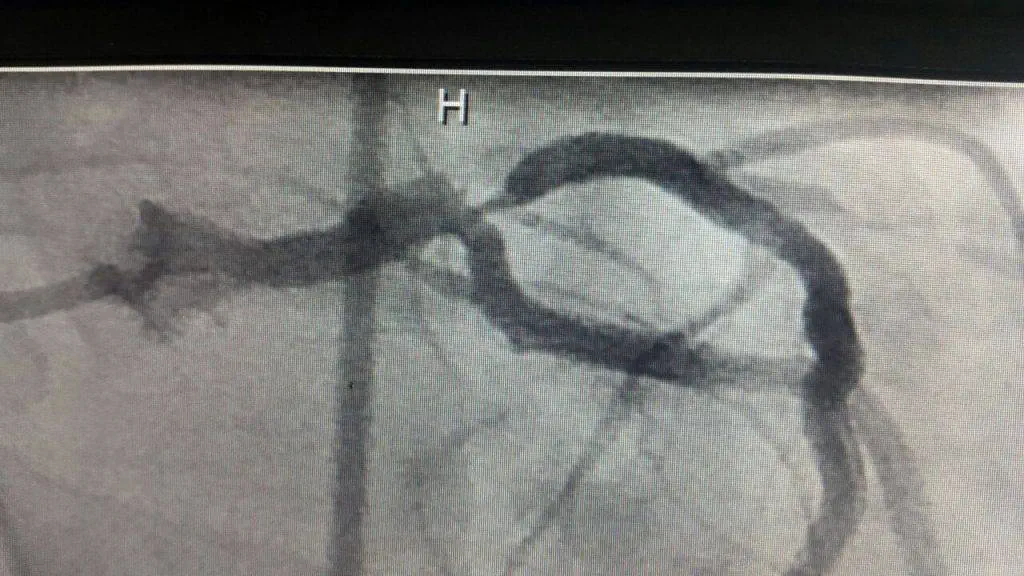

◀ سی تی آنژیوگرافی کم عارضه تر است یا آنژیو گرافی عروق کرونری؟...

آنژیوگرافی سی-تی Computed tomography angiography یا CTA، روشي است كه با استفاده از اشعه X ...